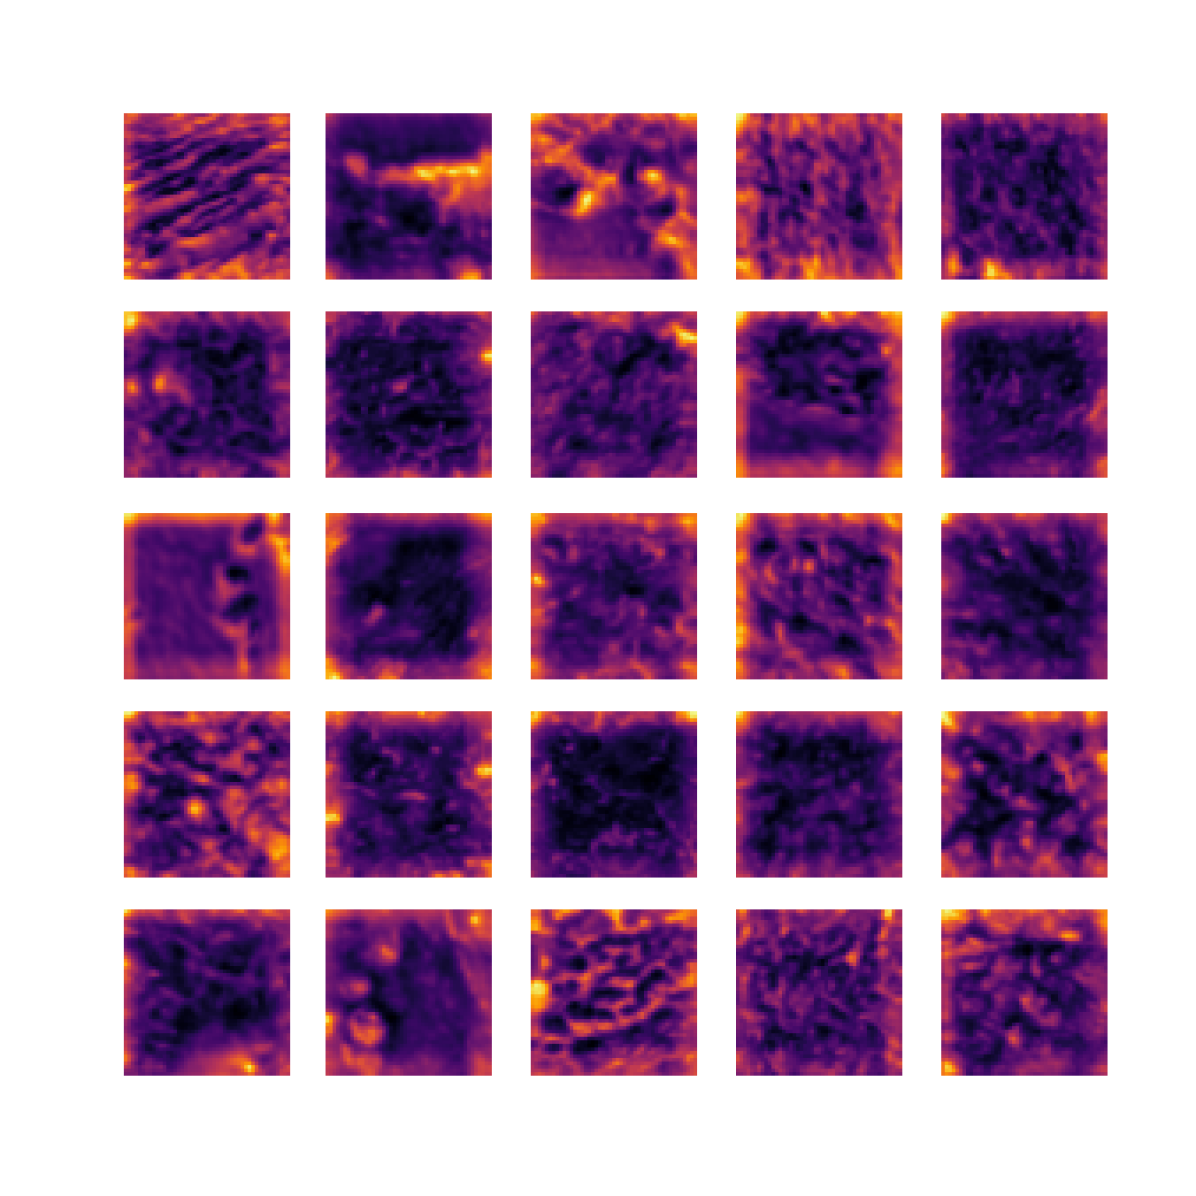

We also analyse the activation maps for each model using GradCAM as described in section S3. This offers more insight into the areas of the image which are contributing most heavily to the models’ representations. In Figure 4(b) we present some representative examples, however, a larger selection which was chosen at random is presented in Figures S10 to S25. The larger selection makes it easier to see the emergent patterns, including that privileged Siamese models tend to mainly identify features which are strongly present in both inputs, while unprivileged Siamese models tend to learn more diffuse features that are not specific to one cell phenotype or image region. TriDeNT ♆ incorporates both sets of features, learning both features specific to the privileged data and more the general features associated with unprivileged Siamese networks.

We can see in Figure 4(b) panel A that for ERG, the privileged Siamese model focuses almost exclusively on any nuclei which could be endothelial cells. As there are very few endothelial cells in the dataset, it could be an effective strategy to identify anything that could potentially be an endothelial cell to minimise the difference between the representations of the H&E model and the IF mask model. In the corresponding unprivileged Siamese image, we see that the model identifies some of these nuclei, albeit less strongly, but also focuses heavily on the other tissue and even the background, while strongly fixating on two spots of debris in the center of the image. This model has less ‘incentive’ to learn the weak features related to endothelial cells as these occur rarely and are not easy to detect, while more generic strong features such as the presence of connective tissue and the prevalence of background are more common and predictable from augmented images. We see that TriDeNT ♆ combines these two feature sets, strongly identifying nuclei while also identifying the connective tissue.

In panel C we see a similar pattern, with the privileged Siamese model fixating solely on the nuclei, while the TriDeNT ♆ model takes a more balanced approach. The unprivileged Siamese model appears to focus on a single cluster of nuclei while neglecting others, and similarly identifies an area of fibroblasts with its distinctive pattern but does not others.

In contrast to panels A and C which represent models with poor privileged Siamese results, panels B and D represent models whose privileged Siamese results were comparable to both TriDeNT ♆ and even the supervised baseline. It is therefore interesting to note that there are far more similarities between the privileged Siamese and TriDeNT ♆ models in both cases. Particularly in panel B, TriDeNT ♆ and the privileged Siamese model return virtually identical heatmaps, with both strongly identifying epithelial nuclei and neglecting the same areas of connective tissue. The unprivileged model in this case appears to focus solely on the centre of the image, giving a significantly different heatmap to the other panels.

Panel D again shows the previous pattern, with the privileged Siamese model identifying the features strongly present in the privileged data – fibroblasts – while neglecting the nuclei present. TriDeNT ♆ also strongly identifies the connective tissue, but, unlike the privileged Siamese model, does not completely neglect the nuclei. The unprivileged Siamese model primarily identifies background, and does not appear to identify the nuclei in this example.